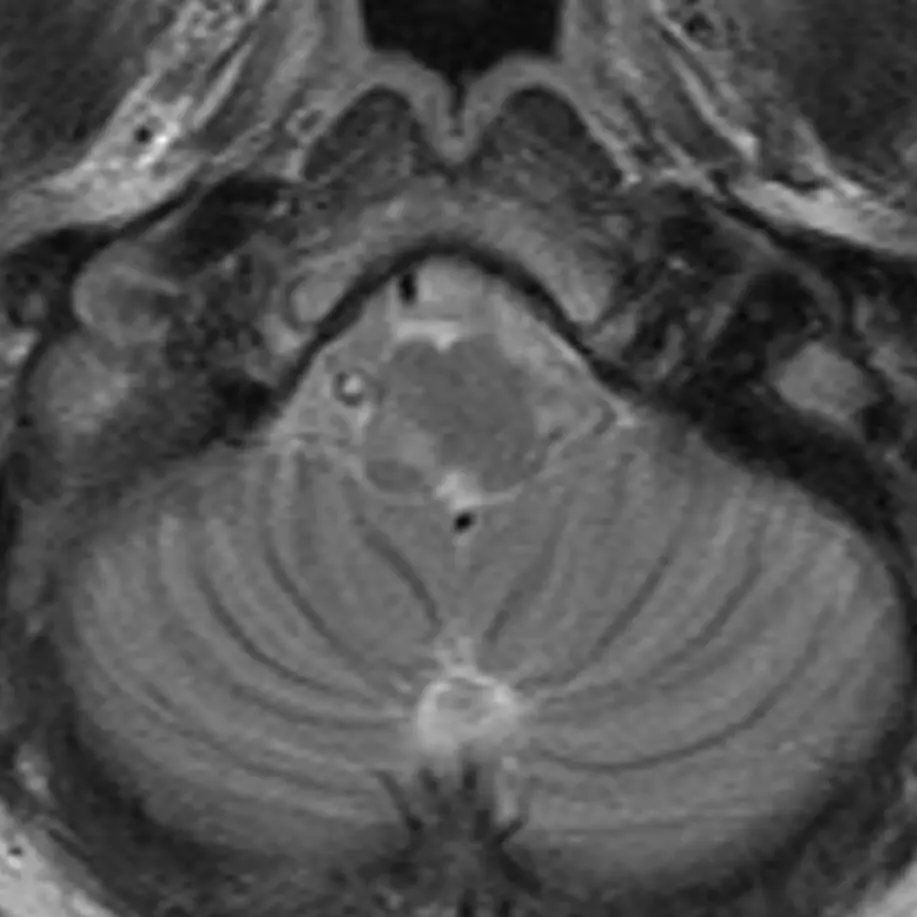

5. Abducens nucleus (CN VI)

The abducens nucleus is located in the dorsal pons at the level of the internal auditory canals. The facial colliculi are the two bumps along the dorsal surface of the pons at this level, which are formed by the facial nerve coursing over the abducens nucleus.

6. Abducens nerve (CN VI)

The abducens nerve courses anteriorly from the abducens nucleus and exits the ventral pons at the pontomedullary junction. After traversing the prepontine cistern, the nerve enters Dorello's canal, where it is relatively fixed in place. It also has the longest subarachnoid course of the cranial nerves. These two features make it particularly susceptible to stretching-related injury, e.g., in the setting of brain herniation. After Dorello's canal, the nerve enters the cavernous sinus, where it is susceptible to mass effect from space occupying lesions, e.g., a mass or a cavernous internal carotid artery aneurysm.

The abducens nerve innervates the ipsilateral lateral rectus muscle, responsible for eye abduction. Damage will cause horizontal diplopia.

7. Facial nucleus (CN VII)

The facial nucleus is located in dorsal pons anterior to the abducens nucleus and posterior to the medial lemniscus.

8. Solitary nucleus

The solitary nucleus is located lateral to the facial nucleus in the lower pons and extends to the upper medulla. It contributes to the facial, glossopharyngeal, and vagus nerves.

Damage to the solitary nucleus may manifest as decreased taste sensation on the ipsilateral tongue.

9. Spinal nucleus of the trigeminal nerve (CN V)

The spinal nucleus of the trigeminal nerve is the inferior continuation of the main sensory nucleus of the trigeminal nerve (see level 3). It is involved in sensation of the head and face. It receives afferent fibers from the facial, glossopharyngeal, and vagus nerves.

10. Facial nerve (CN VII)

The facial nerve courses posteriorly from the facial nucleus before looping over the ipsilateral abducens nucleus and exiting the anterolateral pons at the pontomedullary junction. It then enters the internal auditory canal with the vestibulocochlear nerve (CN VIII). Four nuclei contribute to the facial nerve; the three listed above, and a fourth called the superior salivary nucleus responsible for parasympathetic fibers located medial to the facial nucleus, not pictured here. The nerve has motor, sensory, and parasympathetic functions: